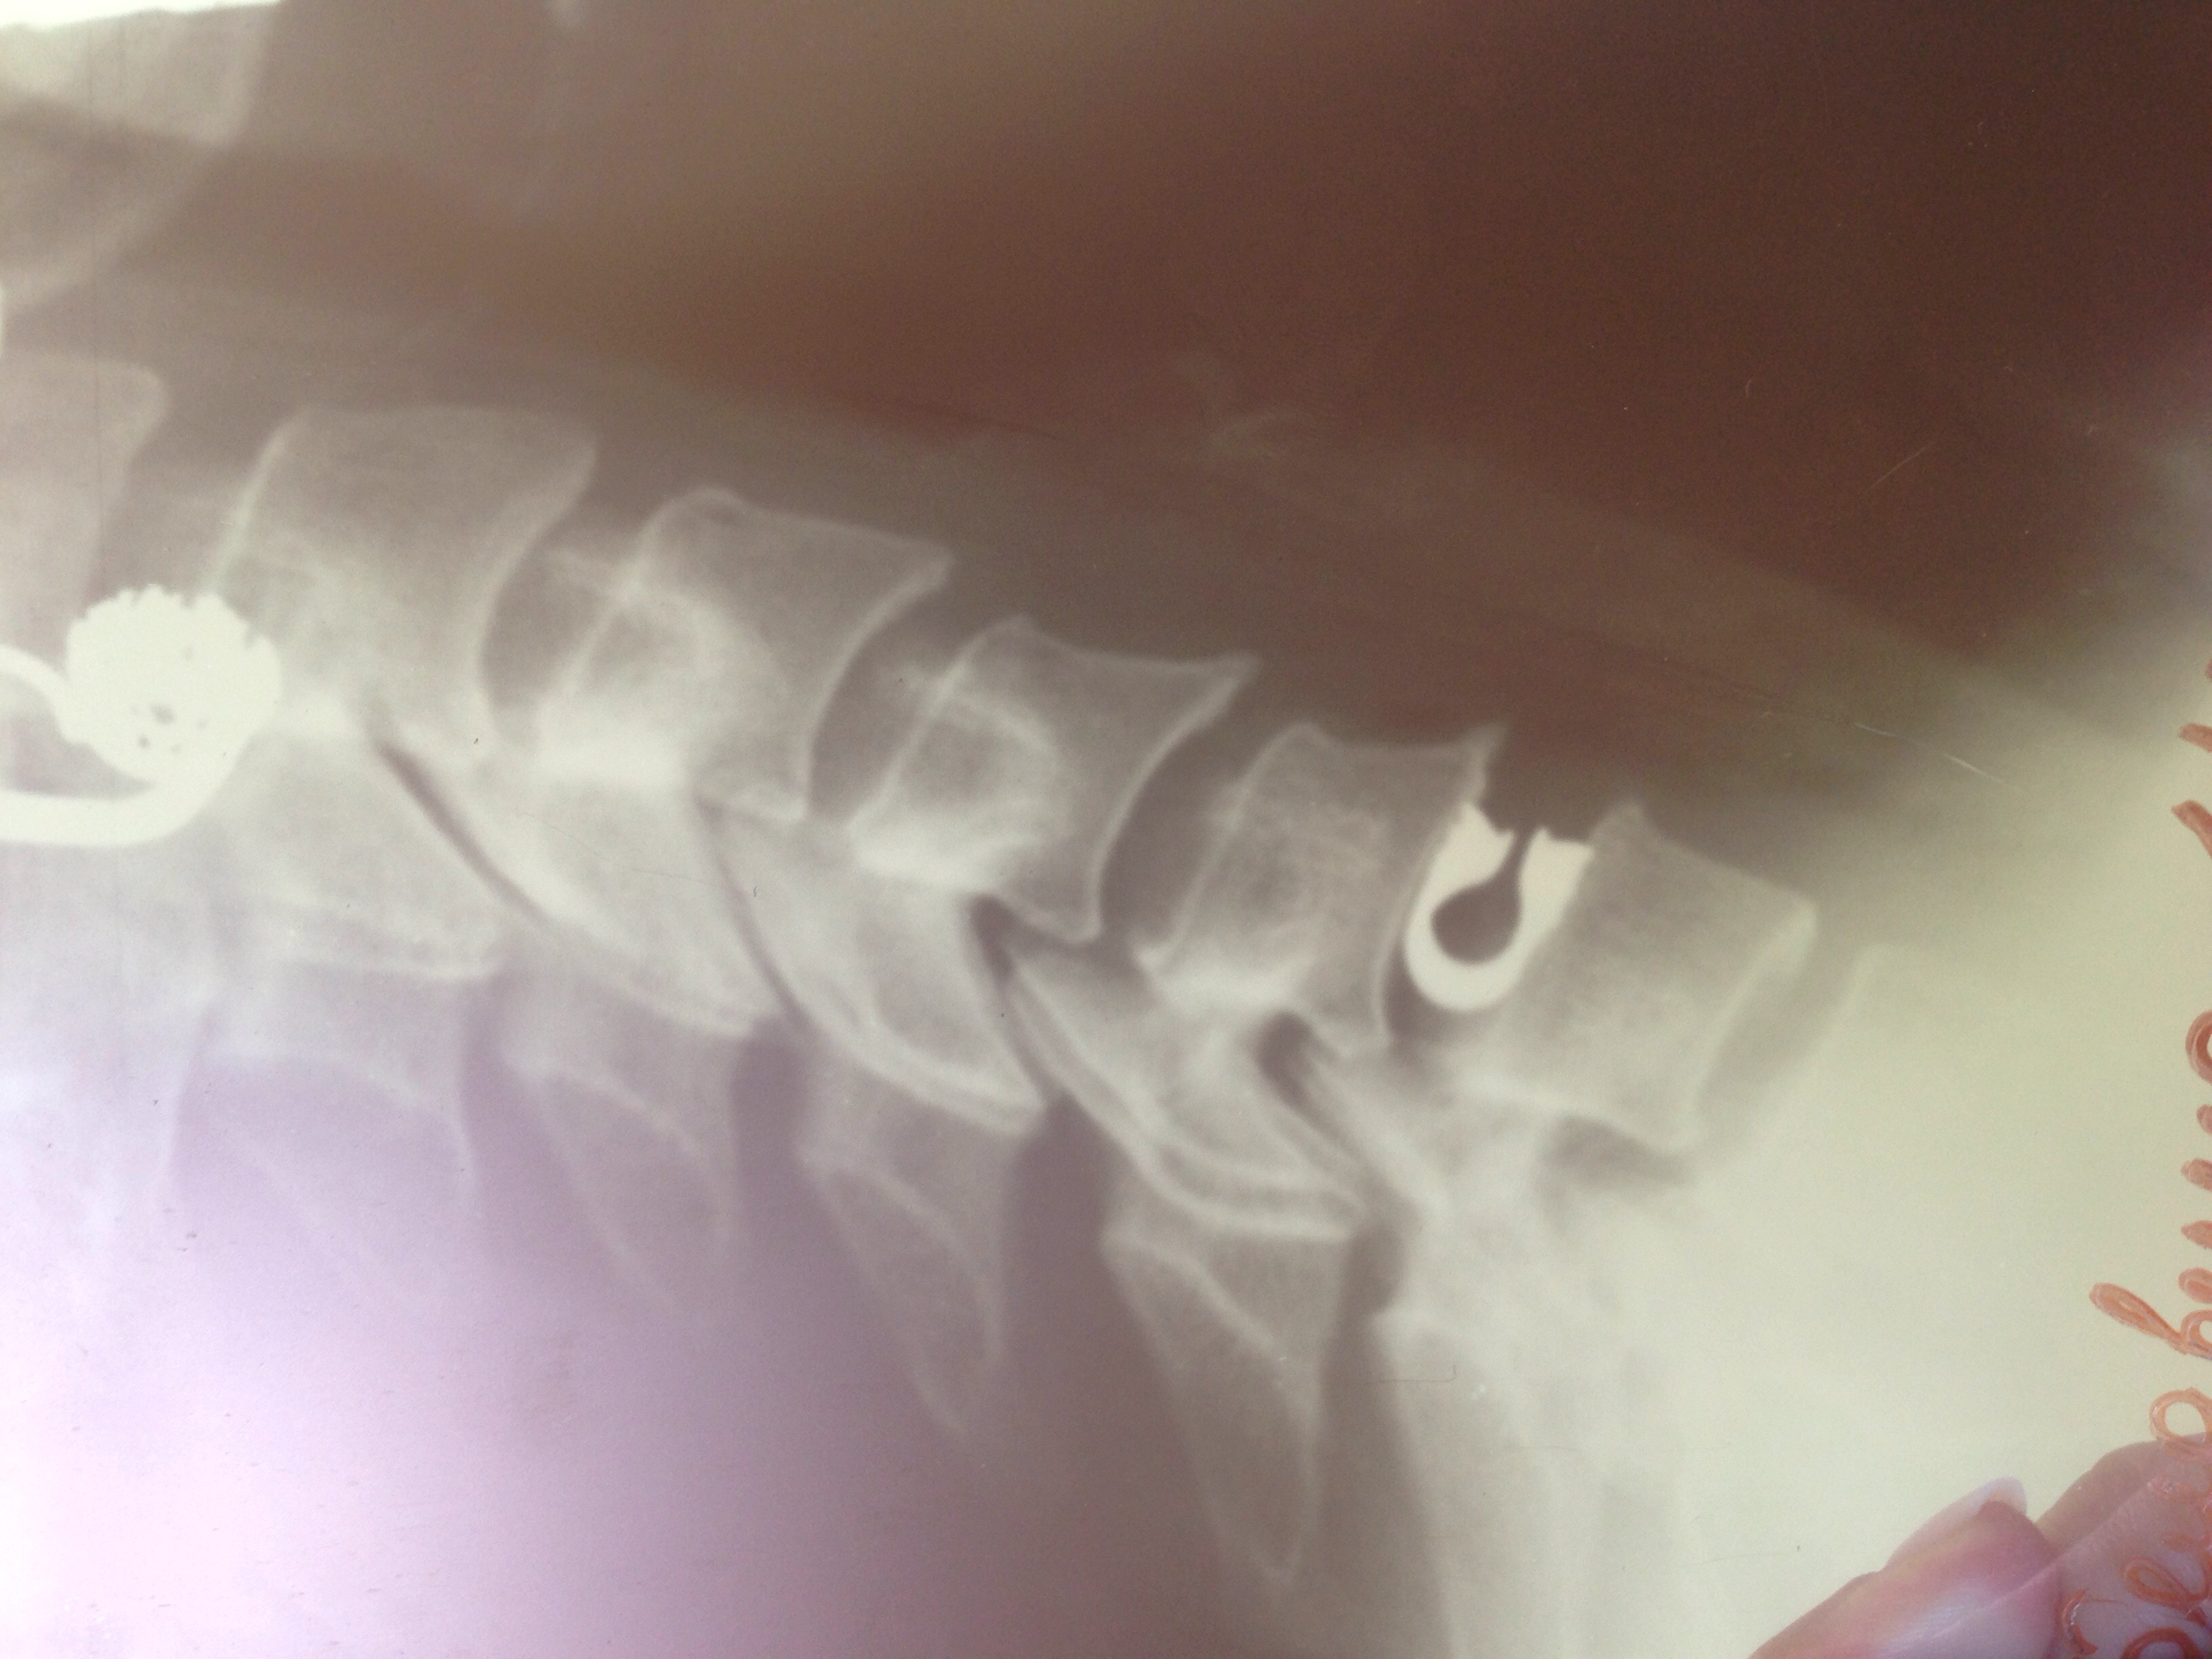

Здравствуйте, мой вопрос может быть не совсем корректен, но проблема мешает жить спокойно. Неделю назад мне была сделана операция по удалению грыжи межпозвоночного диска с дальнейшей установкой динамичного импланта DCI. После рентгена очень засомневалась в правильности его установки и в его подлинности, по той причине , что на рентгенах виденных мною на сайтах компании и просто форумах интернета, он выглядит иначе. Получить консльтацию независимого врача в своем городе не имею возможности.

IMG_0864.JPG

выглядит в этой проекции эксплант нормально, стоит правильно. К импланту всегда прилагается подтверждающая документация.